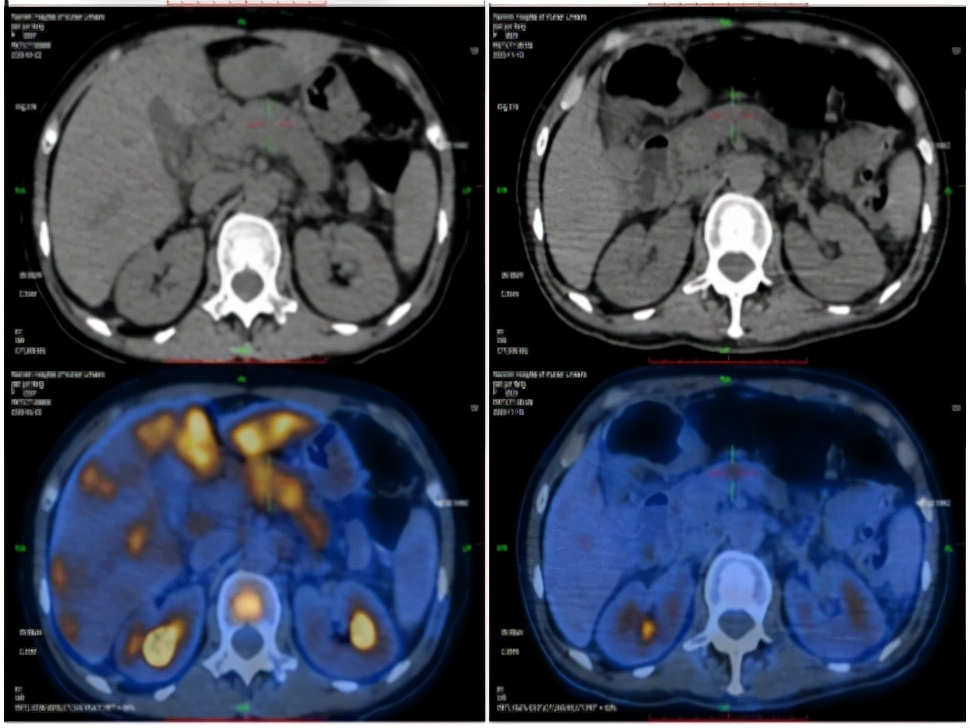

2020-4-22PET-CT提示:1. 胰腺体尾部稍低密度团块;肝内见多发团块、结节灶;肝门区、胰腺周围、腹膜后区多发肿大淋巴结;全身多发骨质密度不均;上述病灶代谢增高,考虑恶性病变,胰腺癌伴全身多发转移;2. 左锁骨上区及胸廓入口处淋巴结,代谢稍增高;不除外转移可能。

PET-CT(2020-04-22)

2020-4-22 2020-11-18